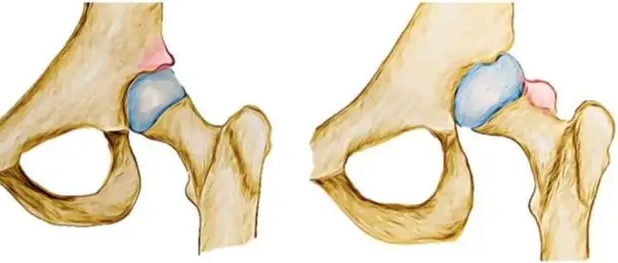

① 관절염

고관절 통증 원인 - 관절염은 관절에 통증과 뻣뻣함을 유발하는 질병입니다. 관절염에는 여러 유형이 있으며 그 중 일부는 나이와 활동에 따른 관절의 점진적인 마모 또는 면역에 의해 발생합니다. 고관절염은 엉덩이 통증을 유발할 수 있습니다. 통증과 뻣뻣함은 아침에 악화될 수 있으며 관절을 움직이면 점차 좋아집니다. 약물과 물리 치료로 통증을 조절할 수 있습니다.